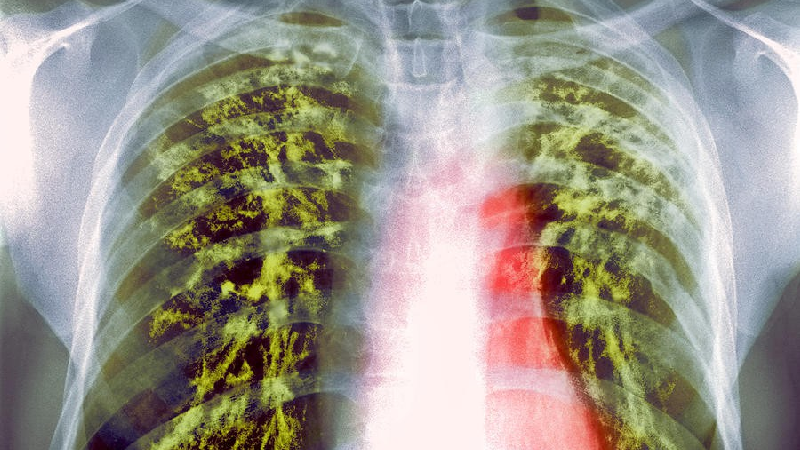

سل می تواند تقریبا تمام اعضای بدن را مبتلا سازد ولی شایع ترین شکل این بیماری، سل ریوی است.

به گفته وی، سل می تواند تقریبا تمام اعضای بدن را مبتلا سازد ولی شایع ترین شکل این بیماری، سل ریوی است.